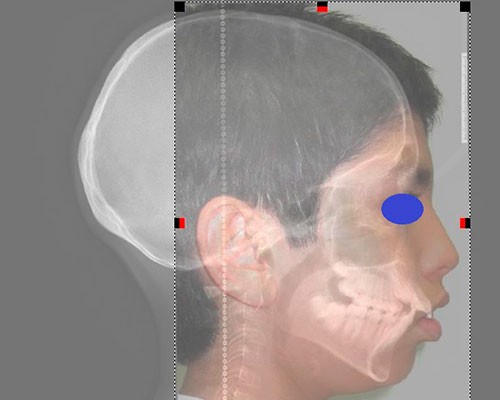

SISTEMAS DIGITALES 3D